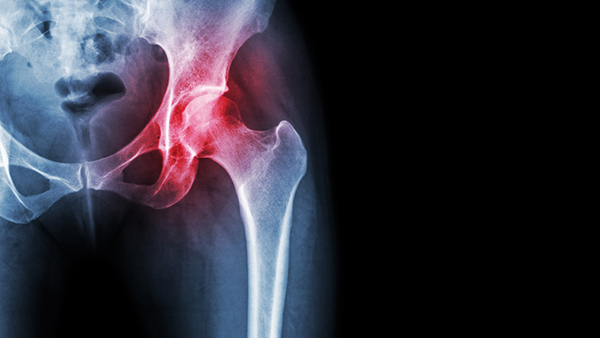

Arthritis Severity on X-Rays Does Not Always Match Pain Levels

One of the most common misconceptions about arthritis is that the amount of damage visible on an X-ray directly determines how much pain a person will feel. In reality, imaging findings and symptoms often do not perfectly align.

For example, some patients may have significant cartilage loss, bone spurs, or joint narrowing visible on imaging studies yet report minimal pain. At the same time, another patient with relatively early arthritis may experience considerable discomfort during daily activities.

Pain perception is influenced by many factors beyond the structural changes within the joint. While imaging helps physicians diagnose arthritis and guide treatment decisions, it does not always predict how severe a patient’s symptoms will be.